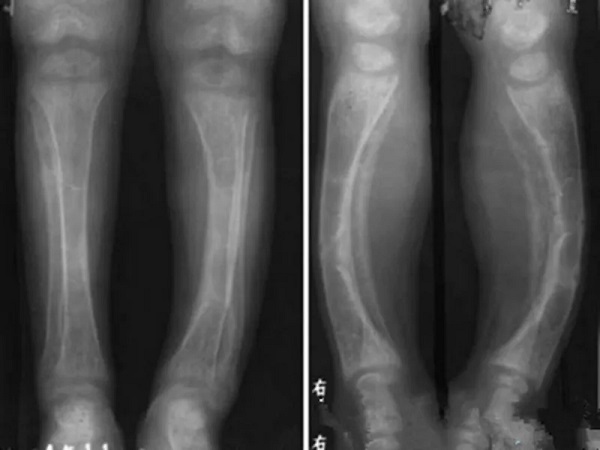

佝偻病儿童的腿型和正常小孩的区别很大

1枕秃:佝偻病早期的时候主要表现为宝宝非常不活跃、脾气比较急躁、睡觉睡不安稳容易惊醒、出汗非常严重,进而就会导致宝宝出现枕秃的情况,但是由于正常宝宝长时间保持一个姿势睡觉也会造成枕秃,所以大家一定要注意区分;2颅骨软化:我们都知道孩子的头骨发育其实还不是很完全,所以宝宝的头部摸起来并不会很坚硬,但是如果宝宝的枕骨、顶骨重点的骨骼出现了弹性的话,那么就是颅骨软化,是佝偻病的典型症状之一;3鸡胸:其实鸡胸也是佝偻病的一种症状和表现,如果孩子的胸骨和邻近的软骨向前突起,形成鸡胸一样的畸形的话,那么也预示着孩子患上了佝偻病;4腿型变化:正常孩子的腿型就是直直的,但是如果孩子患上了佝偻病的话,那么孩子的腿型就会发生变化,可能会出现罗圈腿也就是我们常说的O型腿以及x型腿;5出牙时间:正常的孩子在6个月-18个月的时候就会开始出牙长牙了,但是如果孩子患上佝偻病的话,那么就会因为体内对于钙元素的缺乏而导致出牙比较晚。